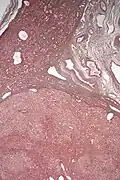

Pathologic diagnosis

Hepatic adenomas are, typically, well-circumscribed nodules that consist of sheets of hepatocytes with a bubbly vacuolated cytoplasm. The hepatocytes are on a regular reticulin scaffold and less or equal to three cell thick.

The histologic diagnosis of hepatic adenomas can be aided by reticulin staining. In hepatic adenomas, the reticulin scaffold is preserved and hepatocytes do not form layers of four or more hepatocytes, as is seen in hepatocellular carcinoma.

Cells resemble normal hepatocytes and are traversed by blood vessels but lack portal tracts or central veins.

Inflammatory hepatocellular adenoma